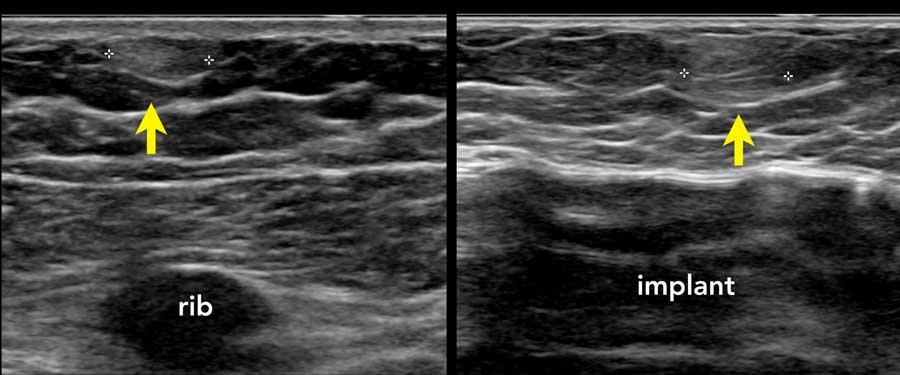

Gần đường giữa, các xương sườn chỉ được cấu tạo bởi sụn và chưa bị vôi hóa.

Sụn không tạo ra phản âm trắng ở mặt trước hay bóng cản âm phía sau.

Thay vào đó, một cấu trúc giảm âm được quan sát thấy phía trước phổi.

Không nên nhầm lẫn cấu trúc này với khối u vú.

Thoạt nhìn, cấu trúc này có thể trông giống u xơ tuyến vú khi hình ảnh xương sườn được cắt trên mặt phẳng ngang.

Khi xoay đầu dò, sẽ nhận thấy đây là một cấu trúc dài liên tục với phần xương sườn đã vôi hóa.